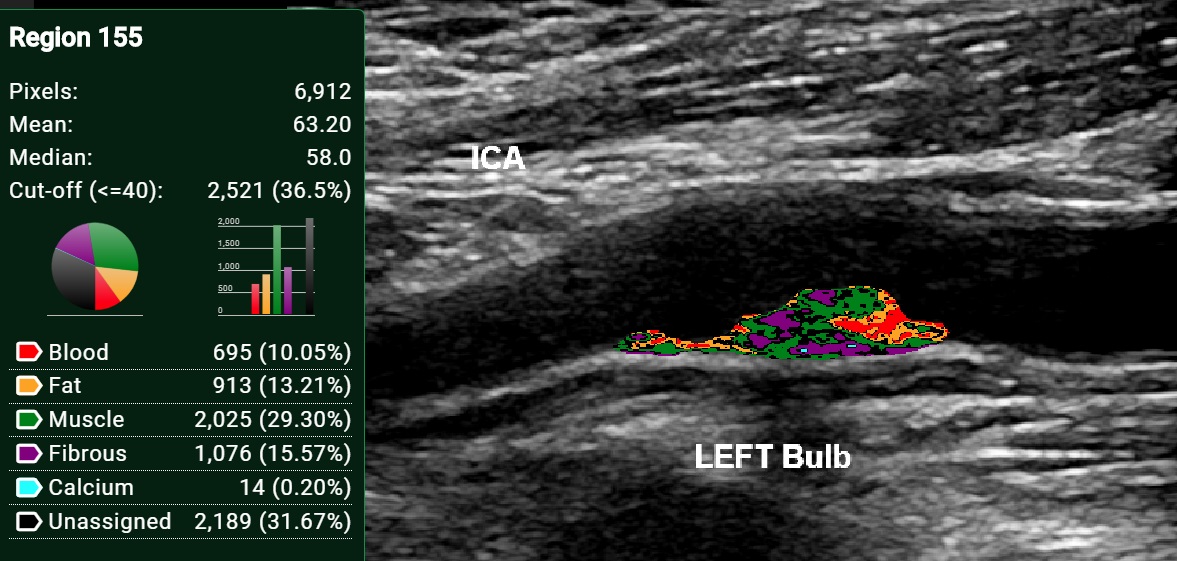

The VANGUARD Study uses ultrasound because it is an inexpensive, radiation-free, non-invasive, portable method that could be ideal for imaging the presence of vulnerable plaque before a heart attack or stroke may occur. To create this new detection tool, our team will be taking 3D ultrasound images from patients undergoing removal of their vessels by our Vascular Surgery department, and analysing this diseased tissue using highly advanced, cutting-edge ultrasound techniques at CINQ and histo-molecular techniques at the Queen’s Cardiopulmonary Unit.